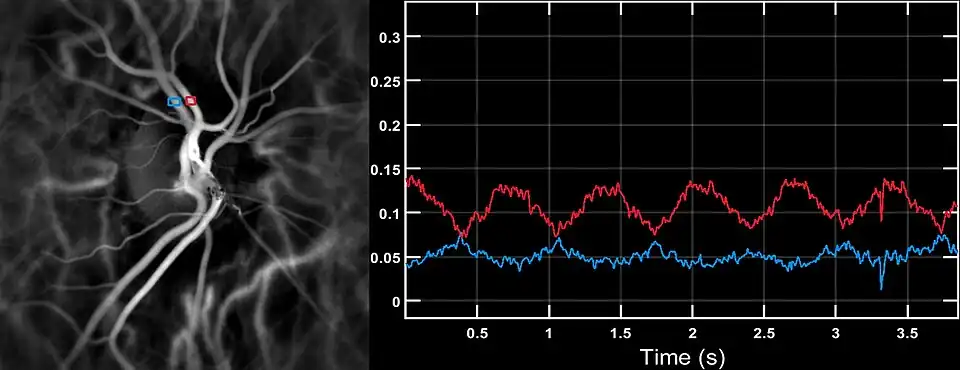

Laser Doppler imaging by near-infrared digital holography can reveal characteristic blood flow waveforms in the central artery and vein of the retina in patients with vascular insufficiency who may exhibit a smooth systo-diastolic pulse in the central retinal artery. This technique enables non invasive functional microangiography by high-contrast measurement of endoluminal blood flow profiles in vessels in the posterior segment of the eye with a spatial resolution comparable to state-of-the-art indocyanine green angiography.